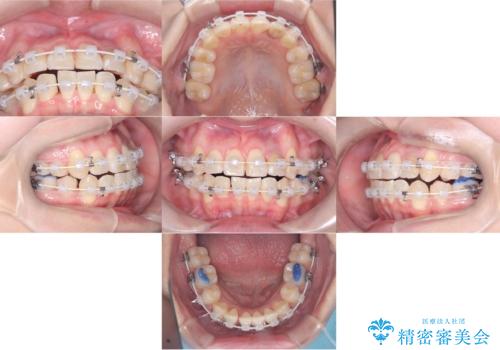

- 治療計画

- 「歯のでこぼこを治したい」を主訴に来院された患者様です。 上下ともに、歯のでこぼこが強く、上下左右4の抜歯をし、ワイヤー矯正で治療を行いました。

かなり綺麗に並ぶ事ができ大変満足していただけました。

叢生量がかなり多かったのですが、歯肉退縮も失活歯も無くとても綺麗な歯並びになりました。

歯のでこぼこは、歯周病や虫歯のリスクも、とても高いので、見た目のみならず、将来の歯の寿命自体もかなり伸ばす事が出来た治療でした。

歯の寿命を伸ばす為には、歯磨きをし易い環境を作る事がとても大切です。